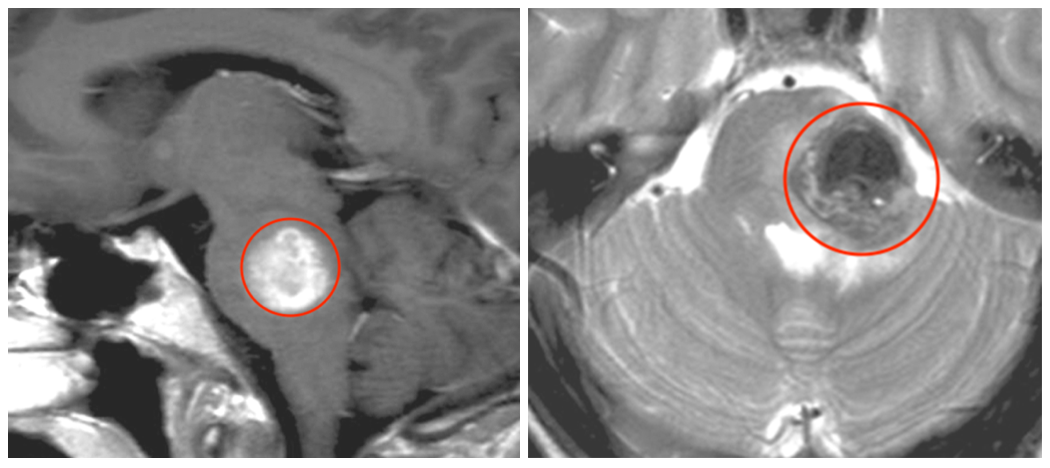

這個(gè)兇險(xiǎn)的顱底腦膜瘤在短短半年間顯露出驚人的侵略性——它從海綿竇這個(gè)“危險(xiǎn)三角區(qū)”發(fā)難,不僅快速向顳窩擴(kuò)張領(lǐng)地,更是一舉攻陷了蝶腭窩和蝶竇這兩大要塞。腫瘤如此迅猛的進(jìn)展態(tài)勢(shì),必須立即手術(shù)解除危機(jī)!

手術(shù)前影像